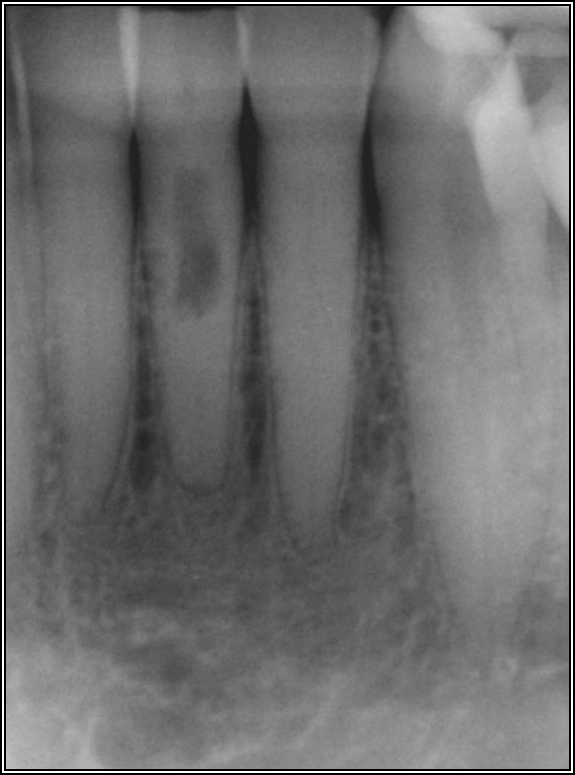

Fig 8. Bitewing revealed decay and other problems.

Figure 8

With the bitewing shown in Figure 8, it became clear there was gross decay in tooth No. 3 that could not be seen on the PA, and there was a periodontal defect, a pulp stone, in No. 2. There was also a class V lesion revealing the bruxism, flat occlusion, multiple restorations in No. 30, a post in No. 31, and decay on No. 2 as well. The post in No. 31 was useless because when a post is placed, it must be the right length, width, and size. If the post is too short, there will be a greater fulcrum and the tooth will break. If it is too long, the clinician can break it by wedging it. If it is too short, it will not hurt the tooth, but it will not provide any valuable function. It is overall preferable to do posts in teeth having just single restorations rather than abutments for bridges because those teeth are already under greater force. If the technique is not performed correctly, iatrogenic issues may result.